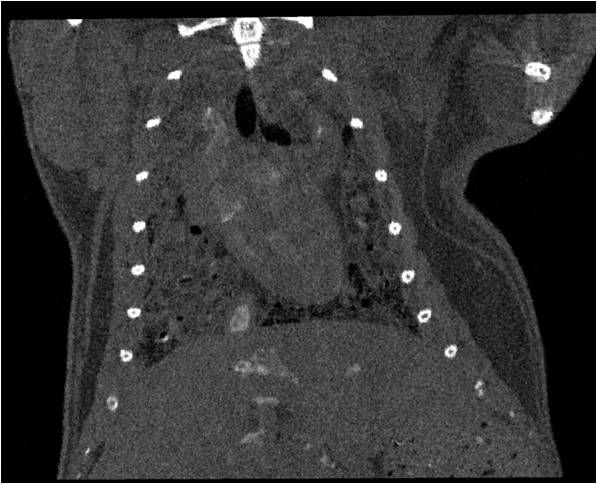

心血管

胸部和心血管的層析成像 胸部和心血管的3D圖像